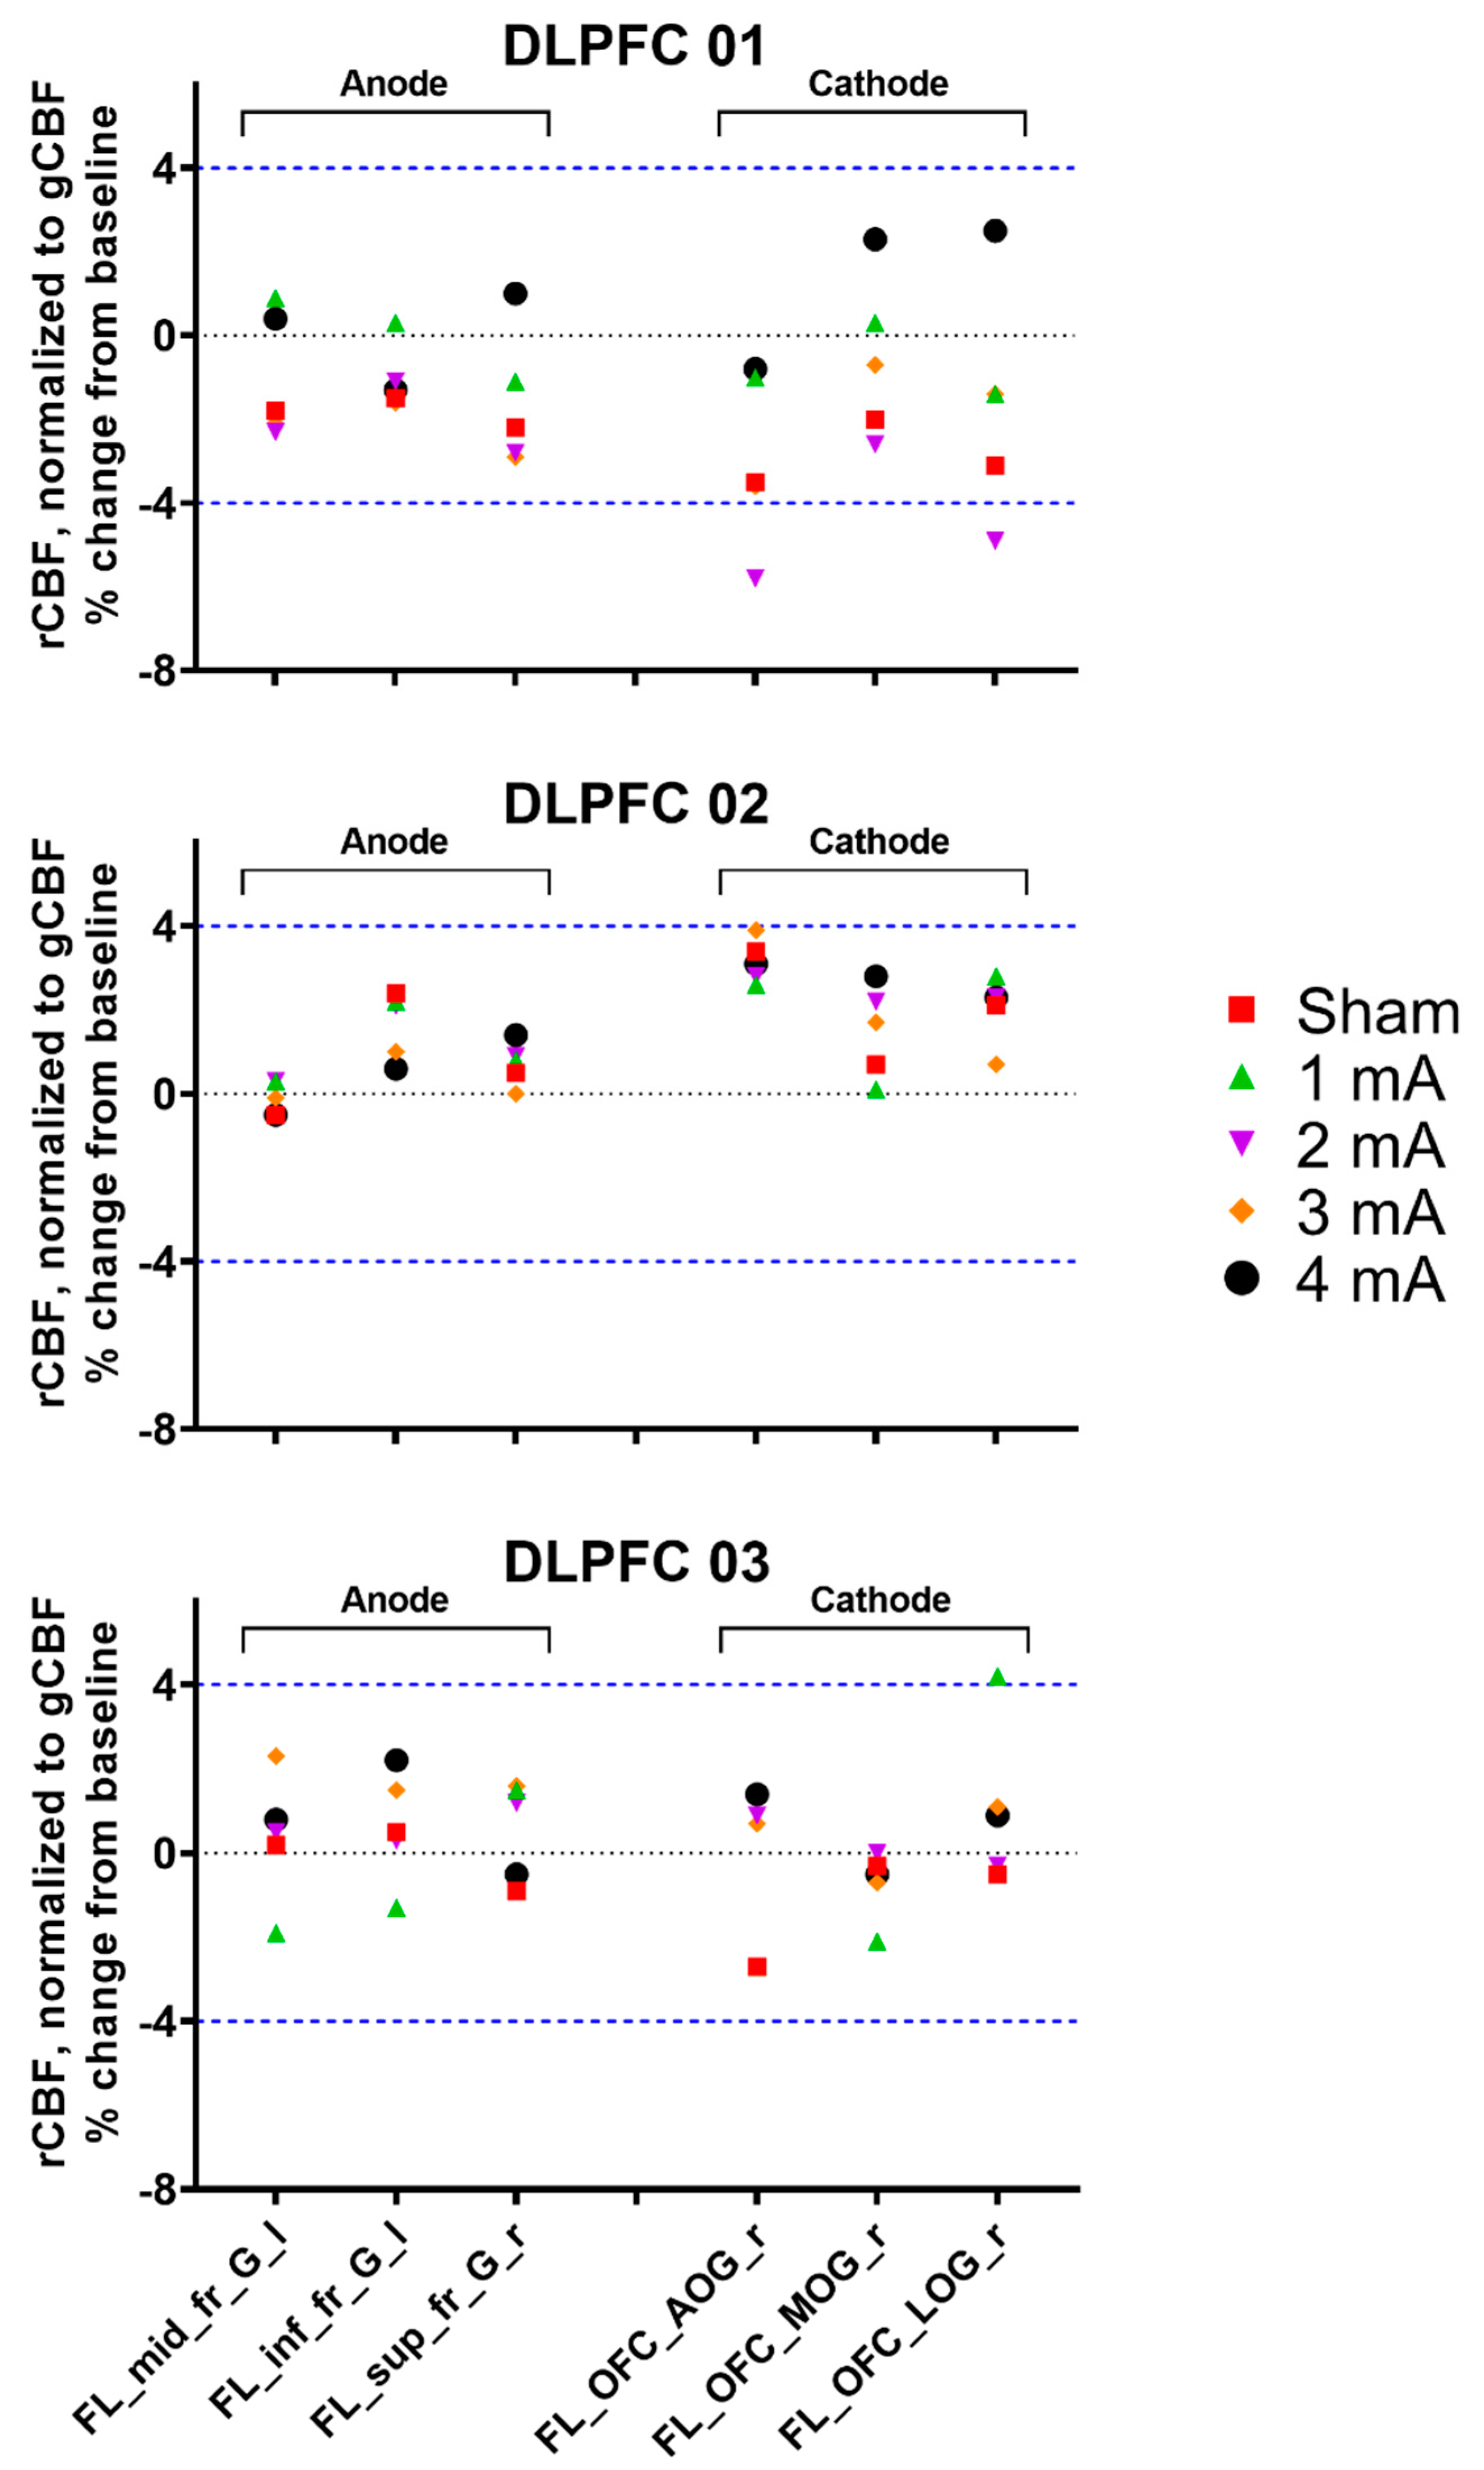

3. Results

3.1. Experiment 1, Dorsolateral Prefrontal Cortex